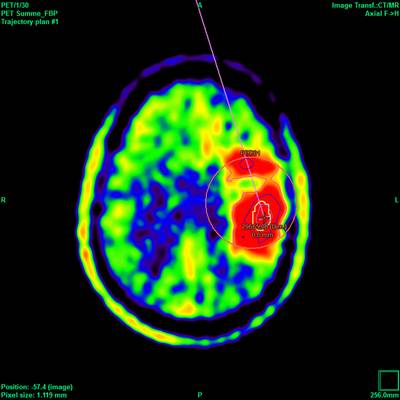

Die hohe Qualität der Bilddarstellung zeichnet das inomed Planning System (iPS) aus. Die automatische Zusammenführung verschiedener Bildmodalitäten ermöglicht eine schnelle und sichere Verifikation der geplanten Zugänge. Diese Zugänge sind für eine erfolgreiche THS zwingend notwendig. Auf Wunsch lassen sich anatomische Atlanten über patientenbezogene Daten projizieren. Dies erlaubt wiederum die Verifikation anhand anatomischer Grundlagen.

Die Planungssoftware iPS von inomed unterstützt sämtliche Planungsansätze, ob „freehand“, funktionell, atlasbasiert oder metabolisch orientiert. Hierfür stehen jeweils verschiedene Möglichkeiten zur Verfügung, die einander ergänzen können. Auch die Option einer Vorabplanung mit Übertragung auf die stereotaktische Bildmodalität gewährleistet die rasche aber genaue Zielpunktplanung am Tag des Eingriffs (THS, Biopsie etc.).

Ein leistungsstarker mehrstufiger Fusions-Algorithmus ermöglicht das Zusammenführen digitaler Bildinformationen, wobei immer der Erhalt der exakten Patienten-Geometrie im Vordergrund steht, bei gleichzeitiger Optimierung von anatomischer Sichtbarkeit und Bildqualität. Dies bildet die Grundlage für sichere Hochrisiko-Eingriffe wie der THS oder stereotaktisch geführter Biopsien.

- Unterstützt werden Bilder von CT, MRT, PET und Röntgen